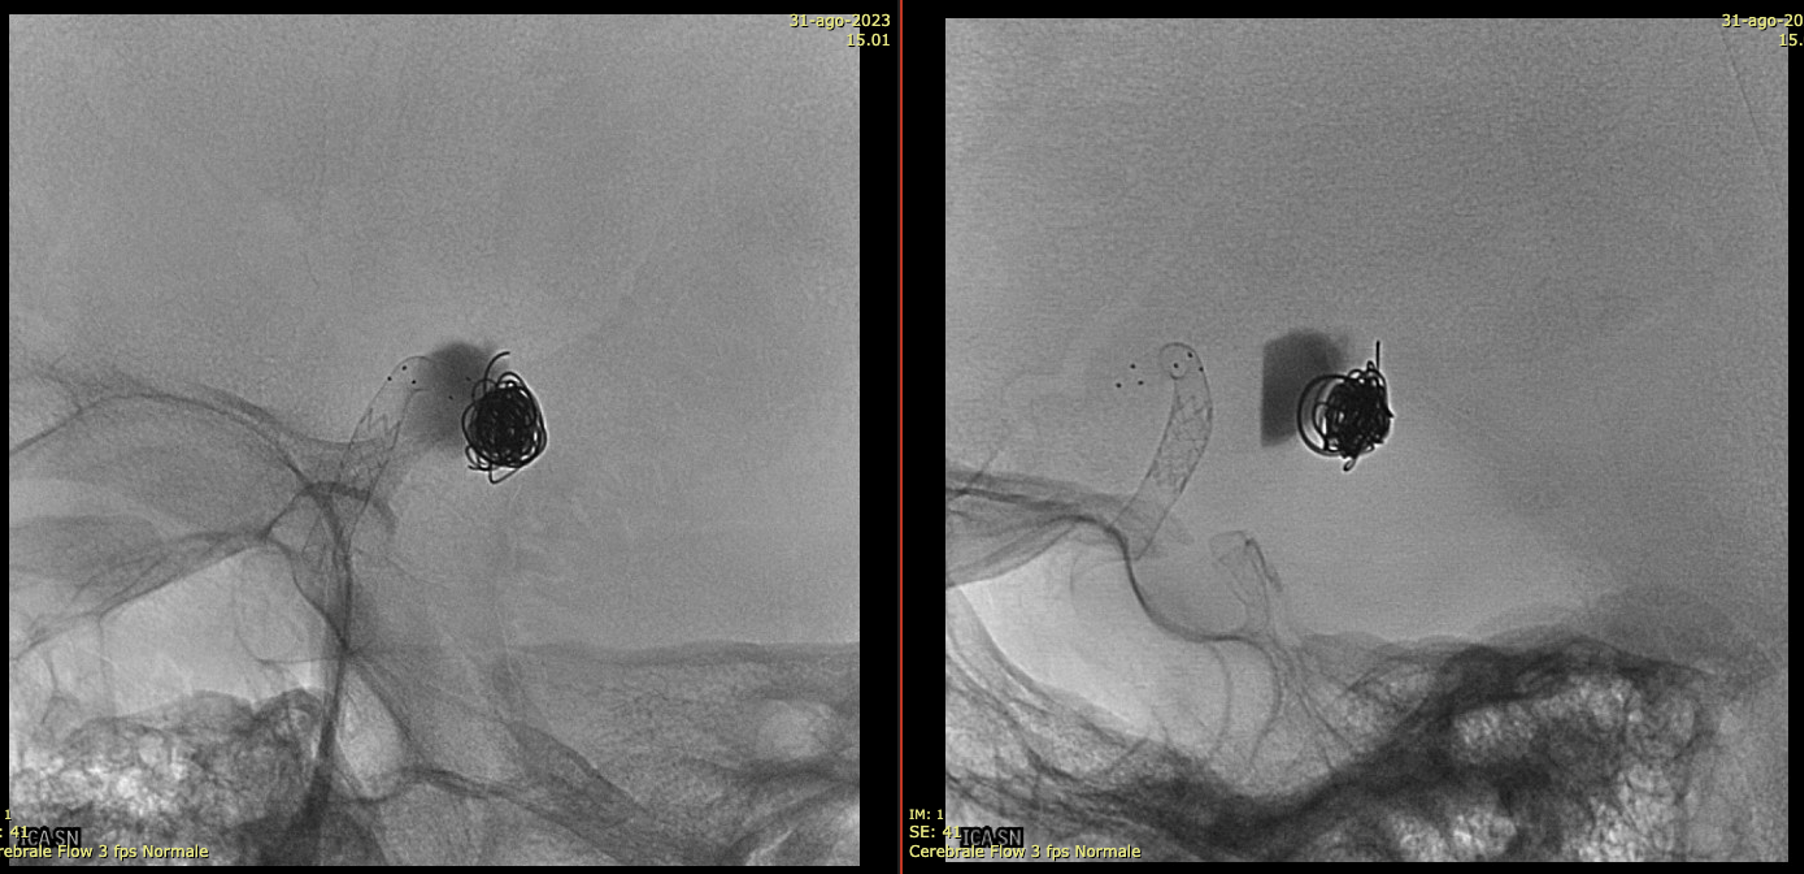

A young man with an unruptured but symptomatic dissecting aneurysm at the origin of the Anterior Choroidal artery. Treated in acute phase with coils; in the meantime the aneurysm has grown.

A Silk Vista was implanted a couple of weeks after coiling

Immediately after the release of the SV, we saw a minimum movement of the distal end to fishmouthing

A Credo stent was used to keep the SV apposed to the vessel wall

One month later the aneurysm was still growing — as they frequently do.

A Bentley Coronary Stent 3 x 8 mm was implanted, progressively inflated (even with a 3.5 PTA balloon) until no more contrast entered the aneurysm. The USA version of Bentley is the Papyrus — Bentley is better.

Noncontrast / dry Vaso-CT, 22 cm FOV 20 seconds acquisition, followed by a secondary reconstruction with 50% FOV and 5123 resolution; Thick MIP.

We can clearly see the three stents. The Credo seems too rigid and probably is not fully open in the curve. The Bentley (arrows) is a little bit overinflated (consider that at this level the coils reduce the image quality). SV is open with some irregularity.

This is the problem with using laser-cut stents for fishmouthing. Alternative is a relatively low coverage braided stent like Evo or LVIS Jr.